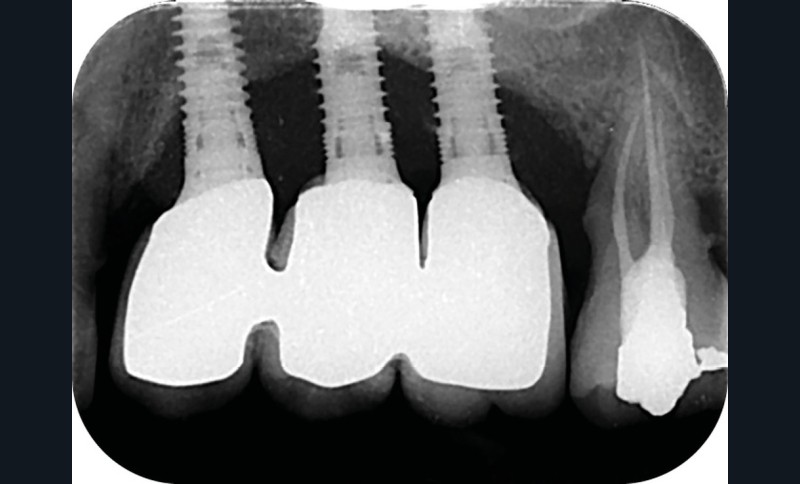

Le nombre d’implants influe aussi sur la survenue de péri-implantite. Dans les reconstructions plurales, l’implant médian est plus à risque de perte osseuse marginale et de péri-implantite [17] (fig. 6 et 7).